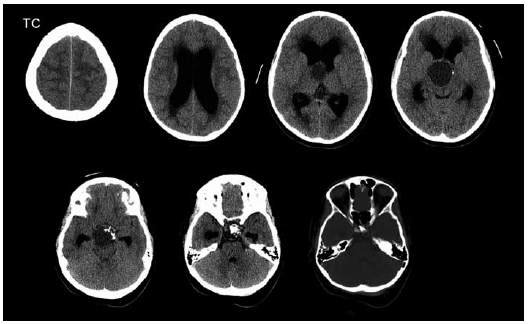

Considere o caso e a imagem a seguir.

Paciente com cefaleia há três semanas. Procurou atendimento anteriormente, mas foi medicado e liberado. Piorou com tonturas e sensação de desmaio e voltou ao pronto-socorro, onde realizaram uma tomografia do crânio.

Em face do exemplo, o diagnóstico é: